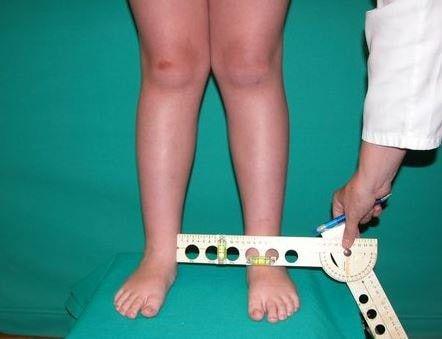

علائم این اختلال

این اختلال در بزرگسالان علائمی را ایجاد می کند که در تشخیص آن کمک کننده هستند:

⦁ فرد به طور کامل حرکت وموبیلیتی خود را از دست می دهد و احساس درد و ناراحتی شدیدی در ناحیه ران می کند.

⦁ فرد همچنین ممکن است احساس کوتاه شدن پا را داشته باشد .

⦁ این اختلال باعث از دست دادن بافت های مفصلی هیپ می شود که به تدریج باعث کاهش توانایی تحمل وزن بر روی هیپ سمت درگیر شده درهنگام ایستادن می شود.

⦁ عضلات اطراف مفصل هیپ دچار تغییر شکل شده و فرد لنگیدن را نیز تجربه می کند.